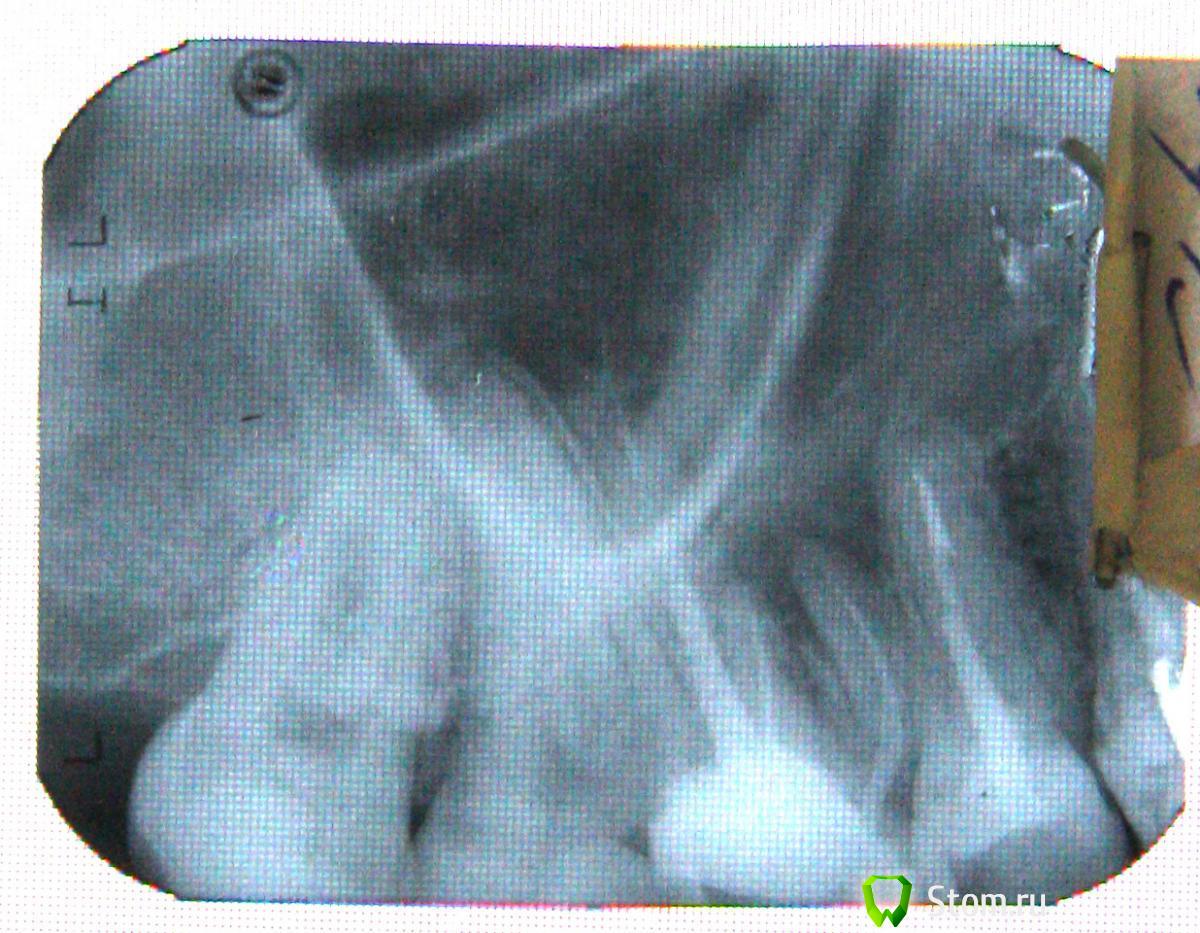

ger_berra Опубликовано 12 декабря, 2011 Поделиться Опубликовано 12 декабря, 2011 Гранулёма есть в области медиального корня(тот,который на снимке ближе к 5-му зубу).В нём в 90% случаев 2 канала.У Вас обработан только один.Снимок не очень хорошего качества,но удалось разглядеть следующее.15 и 16 зубы полностью состоят из пломб,точечного соприкосновения(как задумано природой) нет,поэтому забивается пища->воспаляется десна->появляется кровоточивость и болезненность.Если в 16-м собственных зубных тканей достаточно для протезирования,то его нужно перелечить,т.е. снять пломбу, вынуть штифт, распломбировать,расширить и простерилизовать все каналы.С 15 -м тоже самое. Ссылка на комментарий

Jured Опубликовано 14 декабря, 2011 Автор Поделиться Опубликовано 14 декабря, 2011 А вам не кажется что на длинном корне 16 зуба пломбировочный материал выведен за пределы корня? Ссылка на комментарий

kriokov Опубликовано 15 декабря, 2011 Поделиться Опубликовано 15 декабря, 2011 (изменено) А вам не кажется что на длинном корне 16 зуба пломбировочный материал выведен за пределы корня? по этому снимку однозназно сказать нельзя Изменено 15 декабря, 2011 пользователем kriokov Ссылка на комментарий

Jured Опубликовано 15 января, 2012 Автор Поделиться Опубликовано 15 января, 2012 Ещё нашел место на соседней семёрке со стороны удалённого зуба при лёгком надавливании на которое появляется резкая боль в этом зубе. Может ли быть это последствием удаления 6 или там воспаление и нужно зуб депульпировать? Снимок проблемной зоны выше. На нем как будто бы видно воспаление на корне то и 6 то ли 7.... А вообще при удалении были проблемы. хирург сказал что есть перфорация. Края ранки он немного стянул стянул нитками, но лоскутом ничего не закрывал. Назначил антибиотик ципрофлаксоцин и капли в нос. Зелёные выделения из носа пропали через несколько дней и остались лишь прозрачные. Но по прошествии 3 недель я обнаружил что немного зеленого гноя выделяется прямо в ранке. Там вроде бы не видно никаких даже минимальных отверстий, всё почти зажило, не кровит почти. Ссылка на комментарий